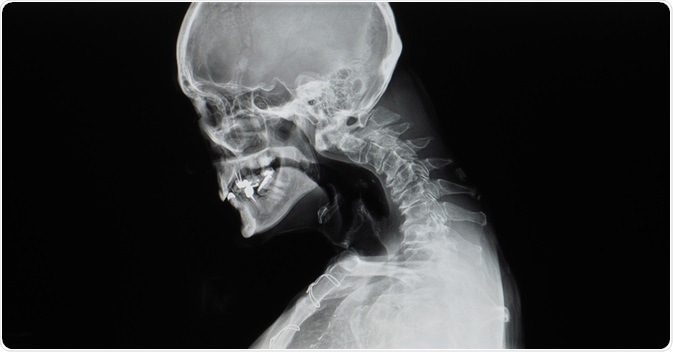

Image Credit: Yok_onepiece / Shutterstock.com